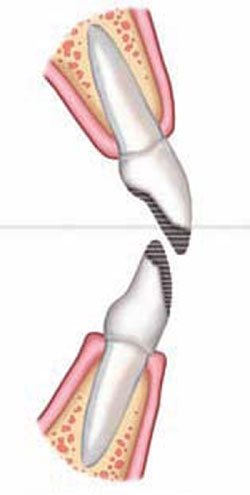

Denture teeth, carefully selected for size and shape, can be reshaped and hollow-ground to resemble veneers (Figure 3D). Similar methods have had good success when used to design implant provisional crowns. This procedure can be performed most efficiently on a diagnostic model in the laboratory to save valuable chair-time. The laboratory steps are tedious, requiring multiple trials and adjustments. It is important that the clinician positions the denture tooth veneers along the long axes of the teeth and resists the temptation to correct misalignments restoratively. This represents one of the more difficult aspects of intermediate restorations for the restorative dentist who, by training, normally restores teeth to the existing occlusion and adjacent tooth structures. Instead, he or she should build to ideal individual tooth anatomy and then allow the orthodontist to correct the proper occlusal and arch-form relationships.

In this case, the plan created during the model-preparatory work was to recontour the soft tissues because of slightly redundant gingival tissues and to remove the primary lateral incisors. The denture teeth were trimmed, thinned, and luted precisely onto the model with block-out compound, and then the positions were registered in a putty silicone index15,16 to facilitate transfer to the mouth (Figure 3E).17 The margins of the veneers are very thin as seen in Figure 3E. The silicone index allows the visualization of the veneer seating process, thereby ensuring proper adaptation to the teeth and easier cleanup. The teeth were prepared very slightly at the line-angles and etched for bonding in the same fashion as conventional veneers. Warmed composite resin (to increase flow)9 was loaded into the denture tooth veneers and pressed onto the teeth. Excess composite resin was removed, and then the veneers were light-cured, finished, and polished. Radiosurgery created a more desirable soft-tissue profile in relationship to bone and to maintain a healthy biologic width.18 The primary lateral incisors were extracted, and the matching denture tooth lateral incisors were sent to the orthodontist for use as pontics on the arch-wire (Figure 3G).

The denture teeth exhibit excellent shape and surface characteristics, and they are very esthetic as well as efficient for the authors’ purposes. They are relatively inexpensive and yet have enough resiliency to withstand the rigors of orthodontic forces for the extended time necessary to complete a treatment process of this nature. As the orthodontic process approaches finishing stages, they may be adjusted easily and refined similarly to the composite resin build-ups.

Long-term provisional stabilization is a significant consideration in these complex interdisciplinary cases because often the provisionals may remain for months or even years.1 Microleakage problems at the margins are common in long-term temporary crowns, whether detected or not, and temporary crown loosening frequently disrupts the orthodontic process. For these reasons, the authors prefer these rather than temporary crowns for long-term use whenever the teeth are amenable to composite bonding. The risks of sensitivity, leakage, and caries are significantly reduced.1 The orthodontist has the ability to recontour and adjust the provisional denture tooth veneers or the composite resin buildups easily as he or she closes spaces, develops proximal contacts, and creates a much more predictable treatment outcome (Figure 3H and Figure 3I). When the teeth are ready for final porcelain restorations, ideal tooth preparations can be made, conserving healthy tooth structure, and thereby helping to preserve tooth vitality and reduce postoperative sensitivity.6

Figure 3C Orthodontics and dentofacial orthopedics were performed to develop arches for optimal future restorative.Mini-implants were used for orthodontic anchorage. |  Figure 3D Denture teeth hollow-ground and luted to model along the long axes of the teeth. Lateral incisors will be extracted. | ||||||

Figure 3E Putty silicone index formed to aid transfer to mouth and denture tooth veneers placed into index. Note the very thin material remaining, similar to porcelain veneers. |  Figure 3F Denture tooth veneers bonded in place in similar fashion to porcelain veneers.Wetting surface with methyl methacrylate monomer and treating with unfilled resin improves bond. | ||||||

Figure 3G Smile view with matching lateral incisor pontics in place on the orthodontic wire. First premolars were converted to cuspids to prevent the need for adjacent anterior implants. |  Figure 3H Occlusal view after 1 year. Veneers are easy to reshape as interproximal and occlusal contacts are developed. | ||||||

Figure 3I Progress at 1 year. | |||||||